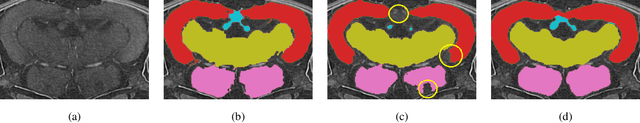

Morphological atlases are an important tool in organismal studies, and modern high-throughput Computed Tomography (CT) facilities can produce hundreds of full-body high-resolution volumetric images of organisms. However, creating an atlas from these volumes requires accurate organ segmentation. In the last decade, machine learning approaches have achieved incredible results in image segmentation tasks, but they require large amounts of annotated data for training. In this paper, we propose a self-training framework for multi-organ segmentation in tomographic images of Medaka fish. We utilize the pseudo-labeled data from a pretrained Teacher model and adopt a Quality Classifier to refine the pseudo-labeled data. Then, we introduce a pixel-wise knowledge distillation method to prevent overfitting to the pseudo-labeled data and improve the segmentation performance. The experimental results demonstrate that our method improves mean Intersection over Union (IoU) by 5.9% on the full dataset and enables keeping the quality while using three times less markup.